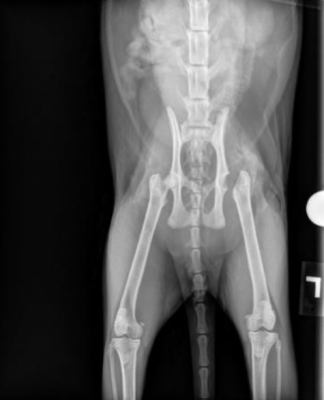

Radiographs of the pelvis and left femur were performed and reviewed by the IVS on staff veterinarian (Dr. Blong) and an IDEXX board-certified radiologist. Imaging revealed a complete, transverse Salter-Harris type I fracture of the left femoral head physis along with delayed physeal closure. This indicated that the fracture occurred at the growth plate and caused a slipped epiphysis.

Based on clinical findings and radiographic interpretation, Dorito was diagnosed with a left femoral head fracture.